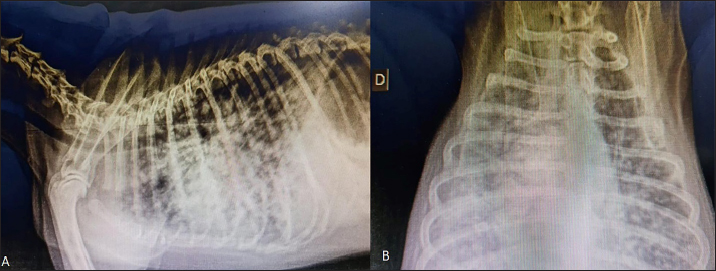

One hundred and thirty days after surgery, the patient started experiencing respiratory distress, and two-view radiographic images suggested distant metastasis (Fig. 4). Unfortunately, the patient died in the clinic and necropsy was not authorized by the owner.

Fig. 4. Radiographic two-view projections of a canine diagnosed with ureteral well-differentiated leiomyosarcoma. (A) Latero-lateral projection showing diffuse multiple nodules in the lungs. (B) Ventrodorsal projection with diffuse multiple nodules suggestive of pulmonary metastasis.